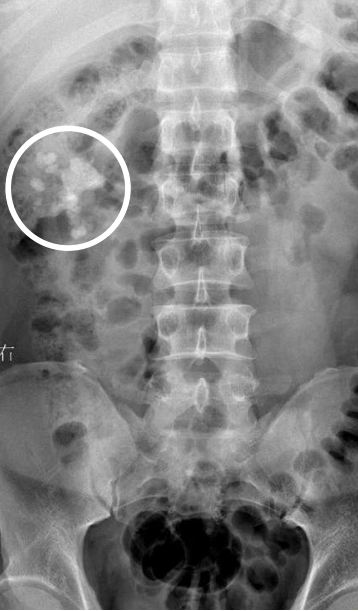

唐先生在医院拍的X光片,图圈系结石,图由医院提供。(图片来源:成都商报)

“针翎钉棘十指牵,暴雨飞星乾坤颠”。巴蜀“唐门”多见于武侠小说,这个传说中擅用暗器的门派,一直给人阴冷奇绝的印象。今年1月,家住三台县,自称“唐门”后人的唐先生住进了医院,不过不是因为“门派争斗”,而是因为双肾结石让他疼痛难忍。经医院检查,其右肾有数颗结石。

自称7岁习武,自幼体弱多病的唐先生,体质后来逐步改善,7岁后就没怎么生病吃药。不过,去年一次肾绞痛,打破了他从不进医院的“神话”。折腾大半年,到今年2月15日,他才从成都一家结石病医院康复出院。据主治医生介绍,造成他双肾结石的原因竟是“练功”,“唐先生每天练功,把尿液憋在膀胱里,通过运动把‘把尿液变汗水’,最终导致尿液的过度浓缩,进而形成结石”。